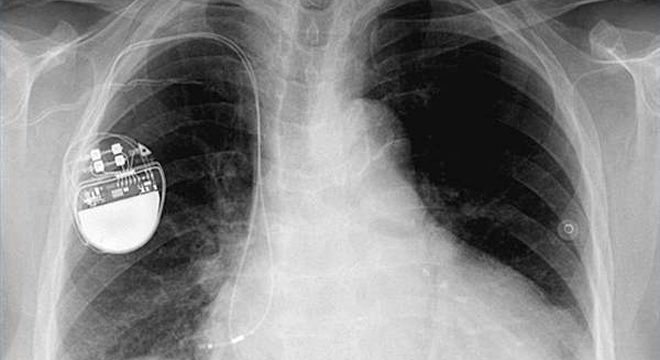

Herzrhythmusstörungen: Ein Herzschrittmacher reguliert den Herzrhythmus

• Einsetzen eines Herzschrittmachers zur Stimulation des Herzens.

• Einsetzen eines automatischen Defibrillators: Dieser hat den Vorteil, dass er nicht nur zu niedrige Herzfrequenzen steigern, sondern auch zu hohe, unregelmässige, lebensbedrohliche Rhythmen durchbrechen kann.